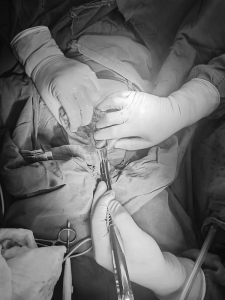

1.患儿:李某某,性别:男,年龄:2岁;简要病史:2岁男孩,因间断腹痛5天,发现消化道异物1天入院。5天前患儿无明显诱因出现腹痛,家长未予特殊重视,1天前患儿出现呕吐伴便秘,就诊于当地医院,行腹部X线片提示消化道异物(磁力球?),遂急诊就诊于我院,诊断“消化道异物(磁力球?)”收住我科。发病后患儿精神食欲差,予以开塞露后排大便1次,小便正常。既往身体健康,无家族遗传病史,心肺腹查体无异常。初步诊断:消化道异物(磁力球?)接下来,患儿需要做什么检查呢?是继续观察自行排出?还是内镜下取出?又或是剖腹探查取出呢?完善腹部X片 (两次间隔时间6小时)显示:磁力球位置未见明显变化(如下图),拟行手术治疗,手术方式为:剖腹探查术。手术探查示 (如下图):胃大弯处可见有2处直径约0.5cm穿孔 (穿孔内取出磁力球5颗),距屈氏韧带约40cm肠管近系膜侧可见2处直径约0.5cm穿孔 (穿孔内取出磁力球10颗),抗菌薇乔全层间断缝合一层胃大弯及小肠肠管穿孔,间断浆肌层加固一层;查无漏气漏液现象,吻合口直径通过顺畅。术毕。术后治疗:予以抗感染、肠外营养、过渡饮食对症治疗,患儿恢复顺利,康复出院。2.患儿:贾某某,性别:男,年龄:1岁10个月;简要病史:1岁10个月男孩,因精神反应欠佳伴烦躁哭闹4天入院。患儿于入院近4天精神反应欠佳,烦躁、哭闹,手捂腹部,呕吐2次,就诊于卫生所予以腹部外敷药物治疗,效果欠佳,后就诊于妇幼保健院,行腹部X片检查,提示消化道异物,自发病以来精神可,食欲欠佳,大便1次,小便量少。既往身体健康,无家族遗传病史,心肺腹查体无异常。初步诊断:消化道异物(磁力球?)完善腹部X片(两次间隔时间6小时)显示:磁力球位置未见明显变化(如下图),拟行手术治疗,手术方式为:剖腹探查术。手术探查示(如下图):距屈氏韧带约30cm小肠有2处直径约0.5cm穿孔(穿孔内取出磁力球1颗、螺丝1颗),距肛门口20cm处乙状结肠近系膜侧可见2处直径约0.5cm穿孔 (穿孔内取出磁力球9颗),据回盲部40cm处小肠系膜可见2处直径约0.5cm穿孔。术后治疗:予以抗感染、肠外营养、过渡饮食对症治疗,患儿恢复顺利,康复出院。